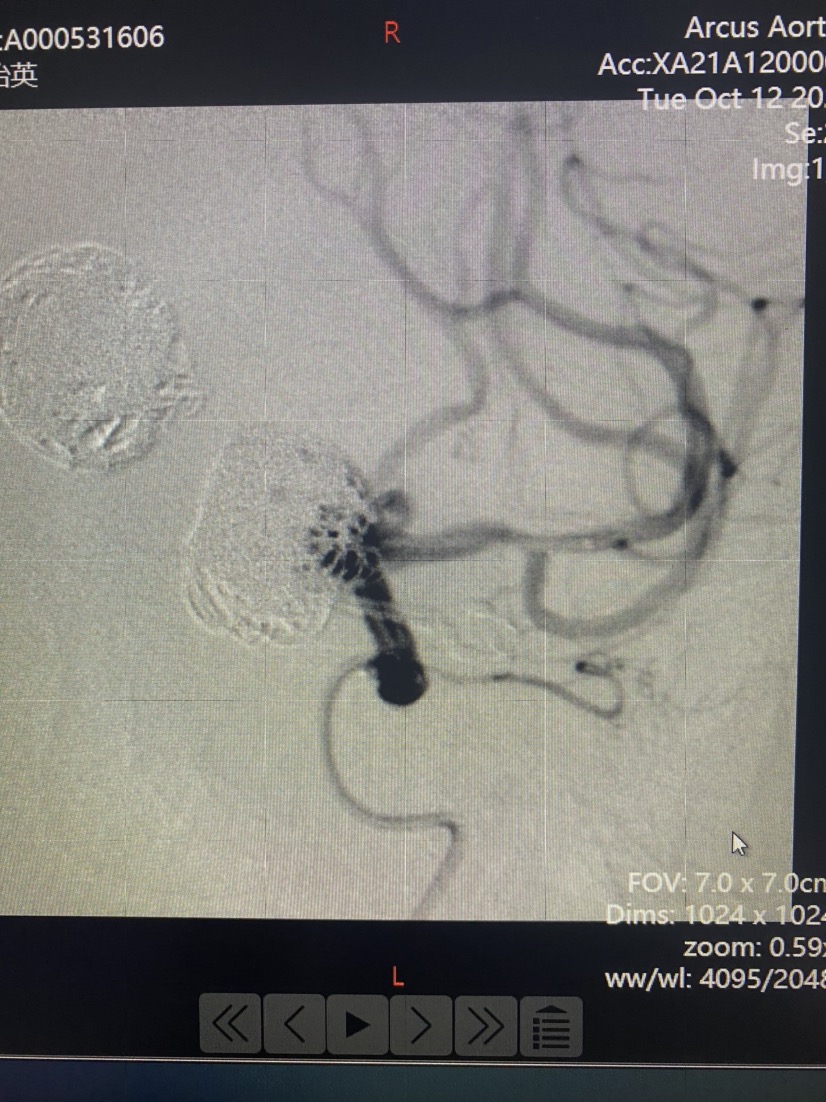

然后填圈至动脉瘤中、上部致密填塞,下部近分支处疏松填塞,同时释放左侧EP2支架,尾端紧贴pipeline侧方呈T形放置。最后稍推拉完全pipeline至基底动脉中下段。(这是本次手术有瑕疵的地方,尾端覆盖基底动脉稍长了一些,与我们测量计算误差有关)

术后即刻造影显示瘤体中上部已完全不显影,仅下部可见造影剂,基底动脉各分支显影良好。

DynaCT显示pipeline打开贴壁良好。